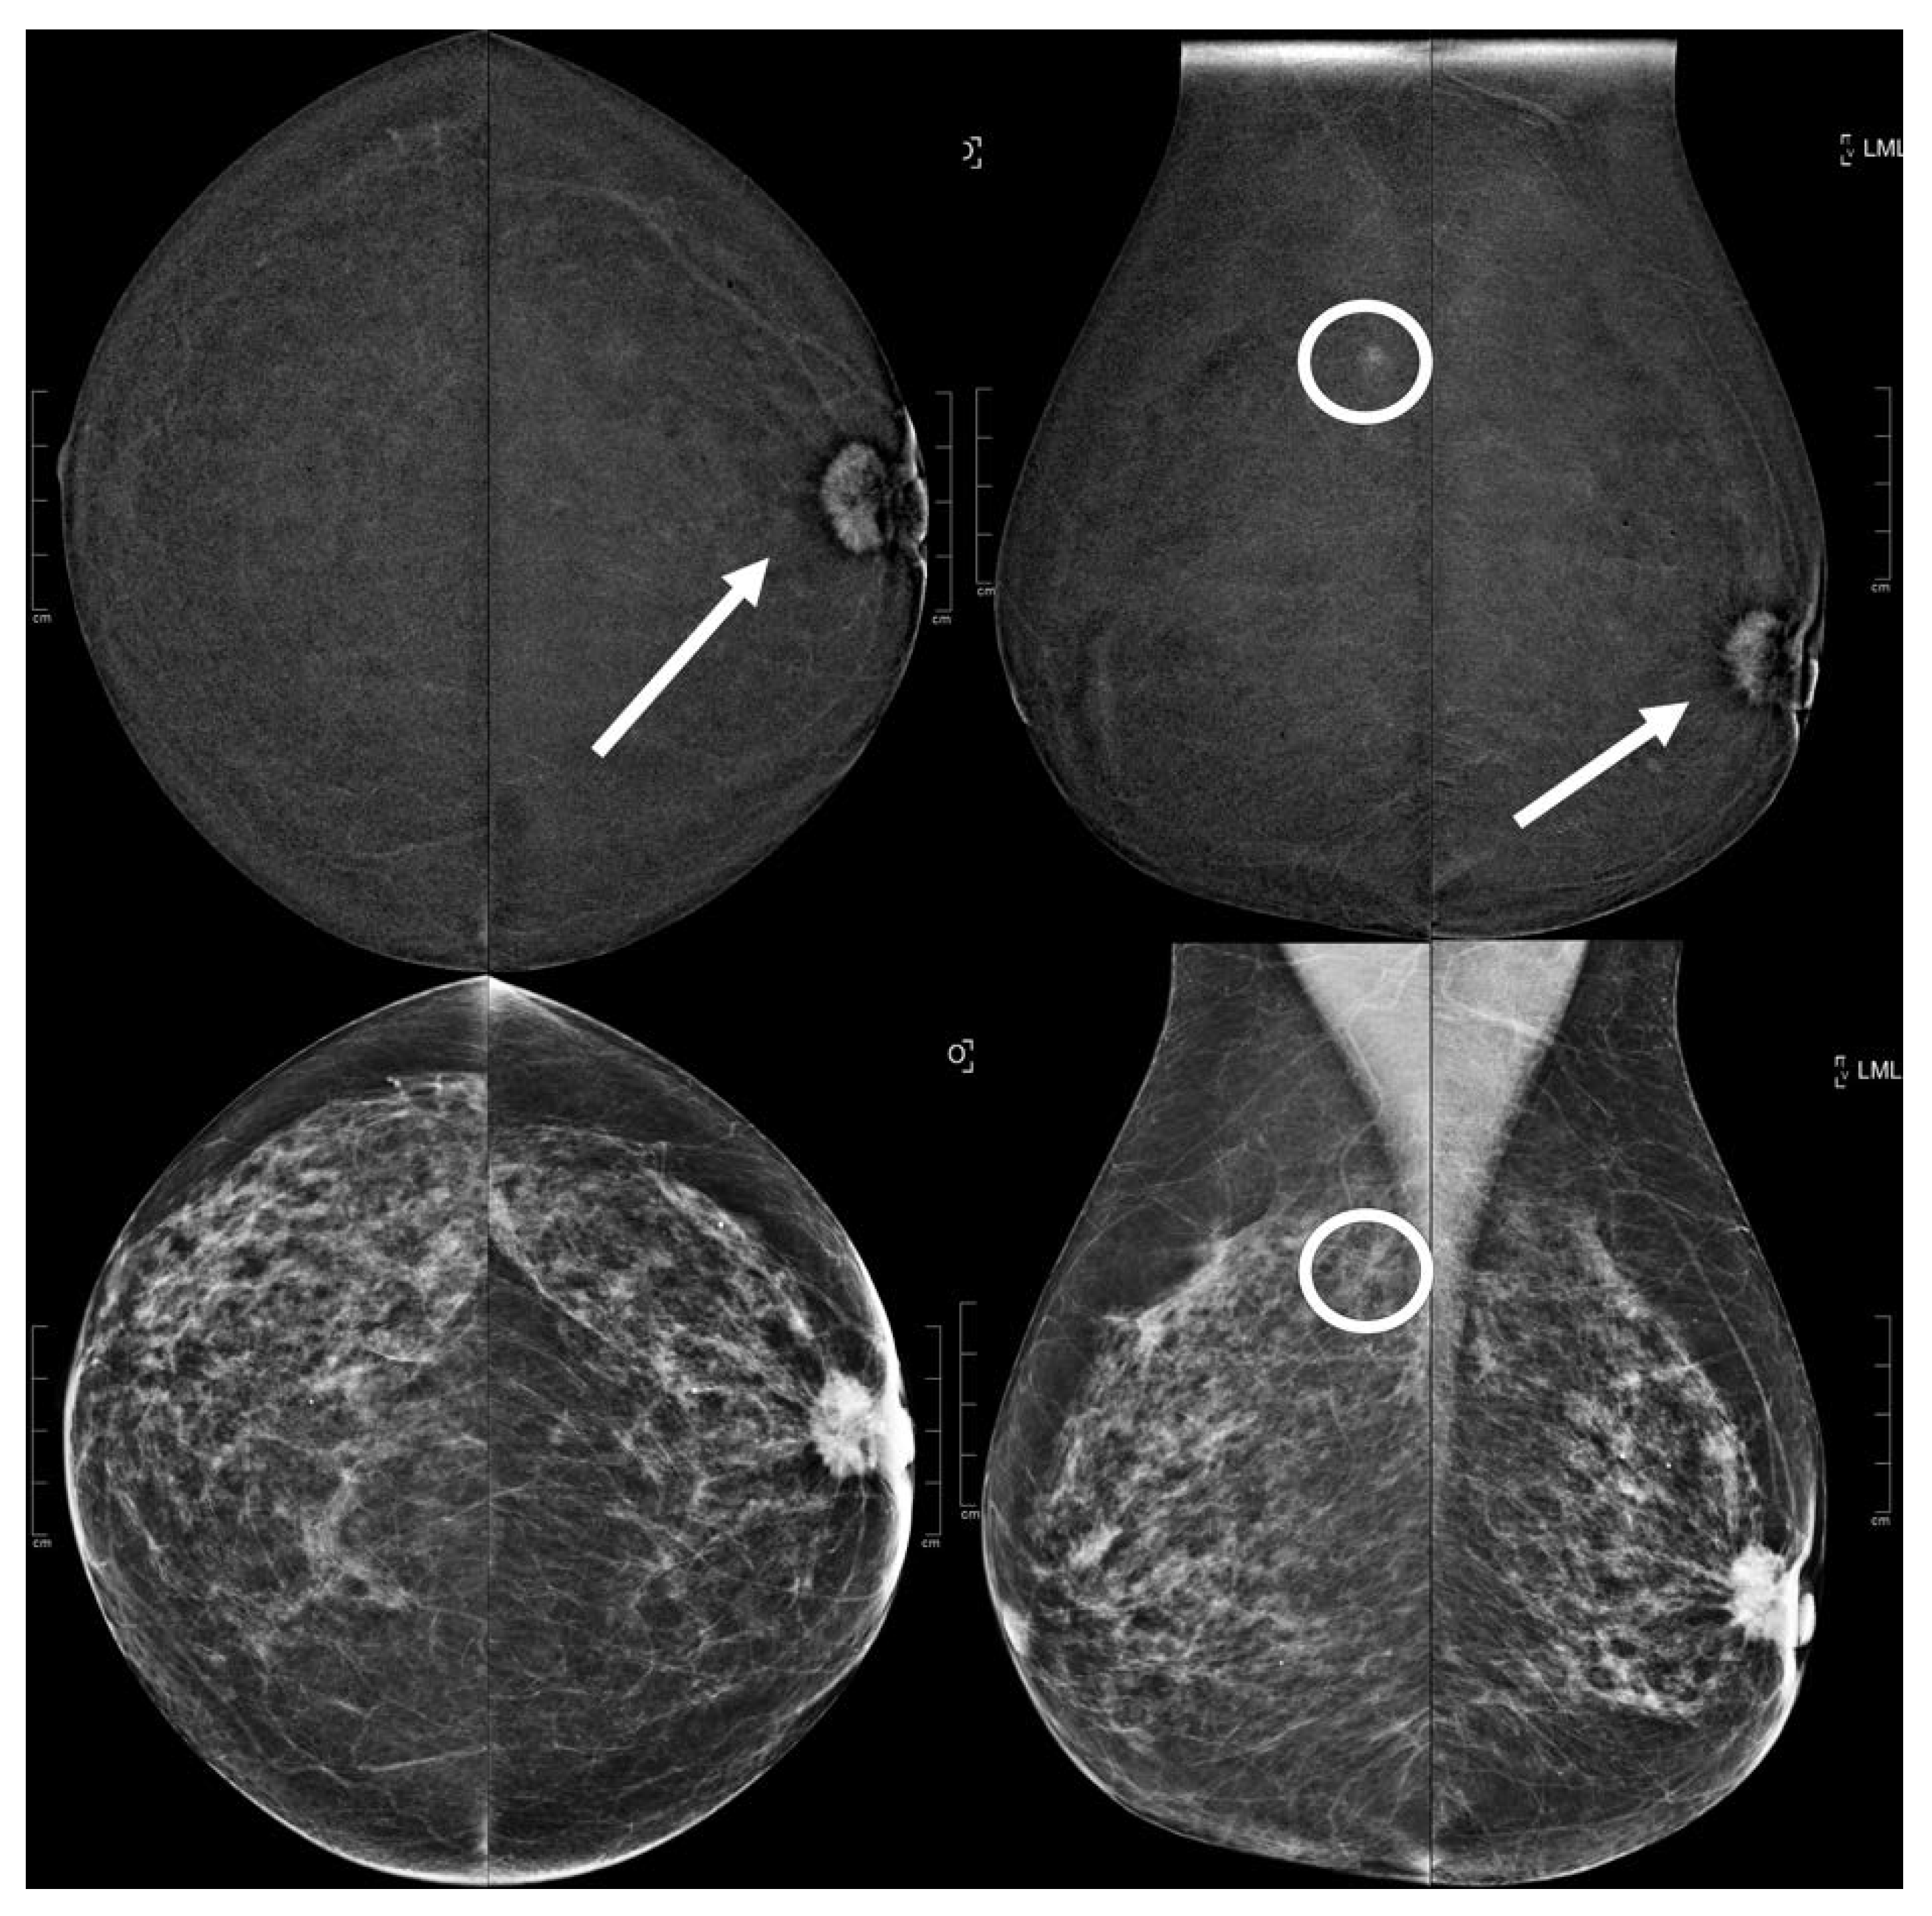

Figure 3.

A 73 year old patient. Contrast-enhanced digital mammography performed as preoperative staging for a B5 lesion in the left breast (arrows). In the early RC in the right breast, there was an enhancing asymmetry in the upper quadrants with high conspicuity only visible in MLO (circle). The EA did not have a clear correspondence in low-energy images. The patient underwent SL-US, which showed a hypoechoic mass of 6.0 mm that was subsequently subjected to CNB (core needle biopsy), which confirmed an invasive tubular carcinoma.